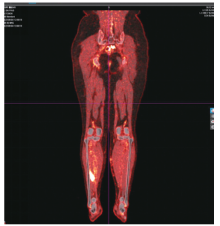

宫颈癌罕见小腿肌间转移1例

宫颈癌肌间转移不常见,小腿肌间转移尤为罕见。现报道1例宫颈癌小腿肌间转移病例。目前针对远处肌间转移的宫颈癌治疗虽无统一的治疗标准,但仍以多学科会诊为主,争取给患者获得更多的治疗选择和生存机会,使患者获益最大化。